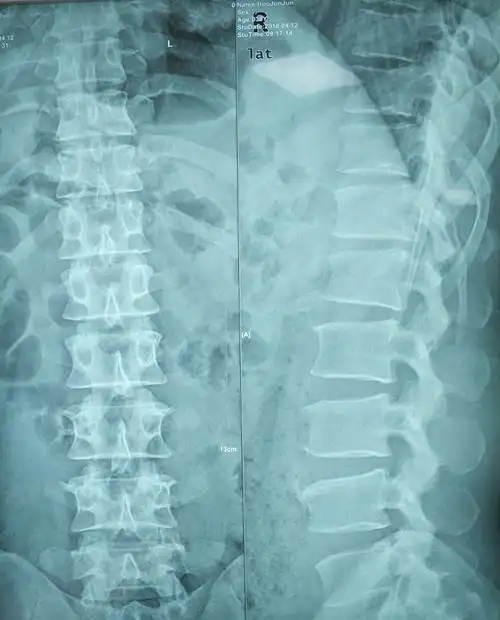

【病例快讯】经皮脊柱内镜技术治疗胸腰段椎间盘突出症(t12-l1)